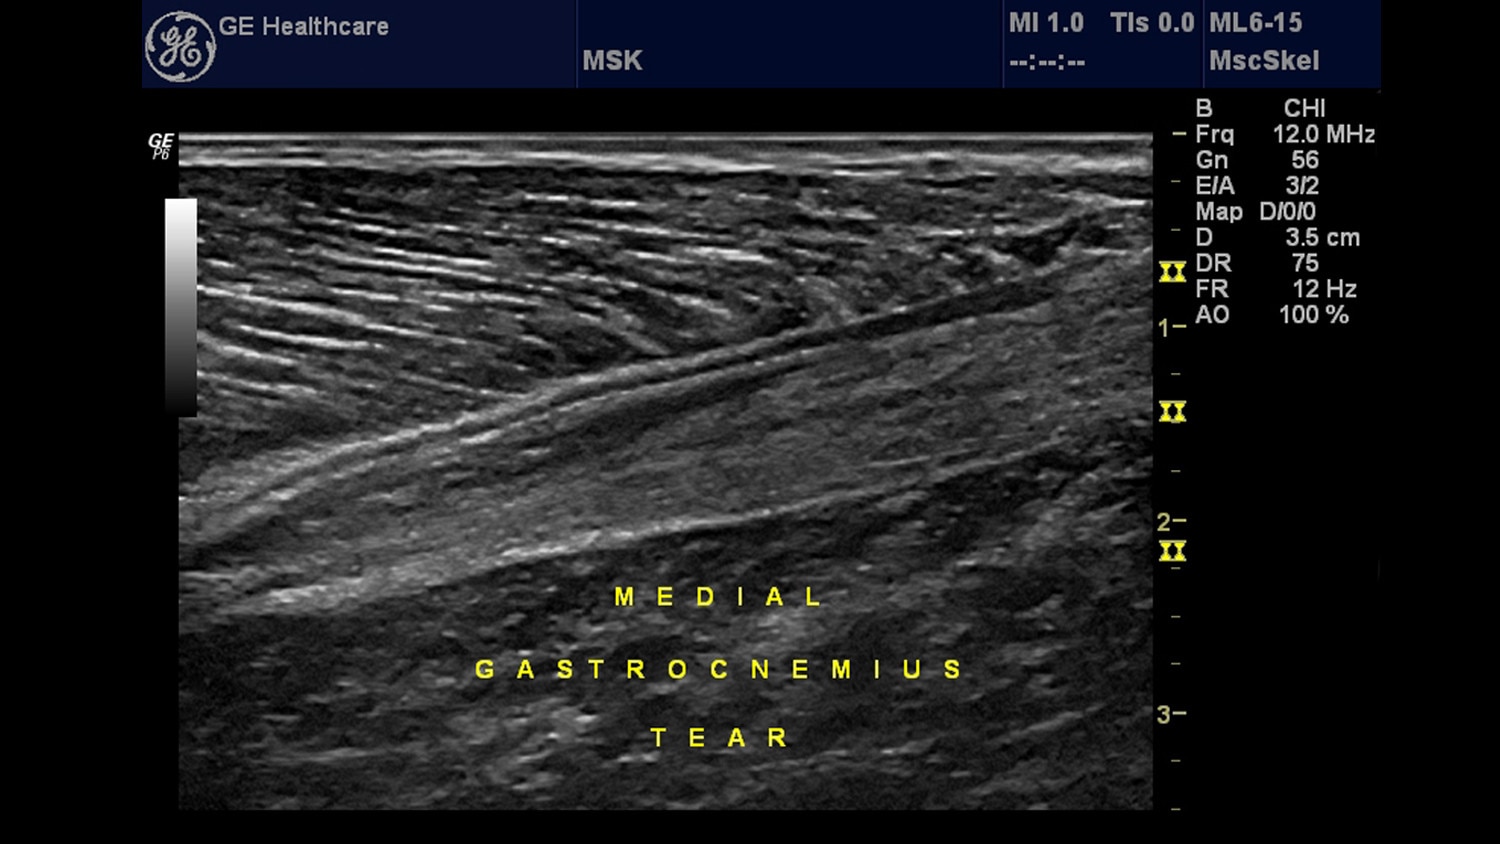

Musculoskeletal (MSK)

Ultrasound